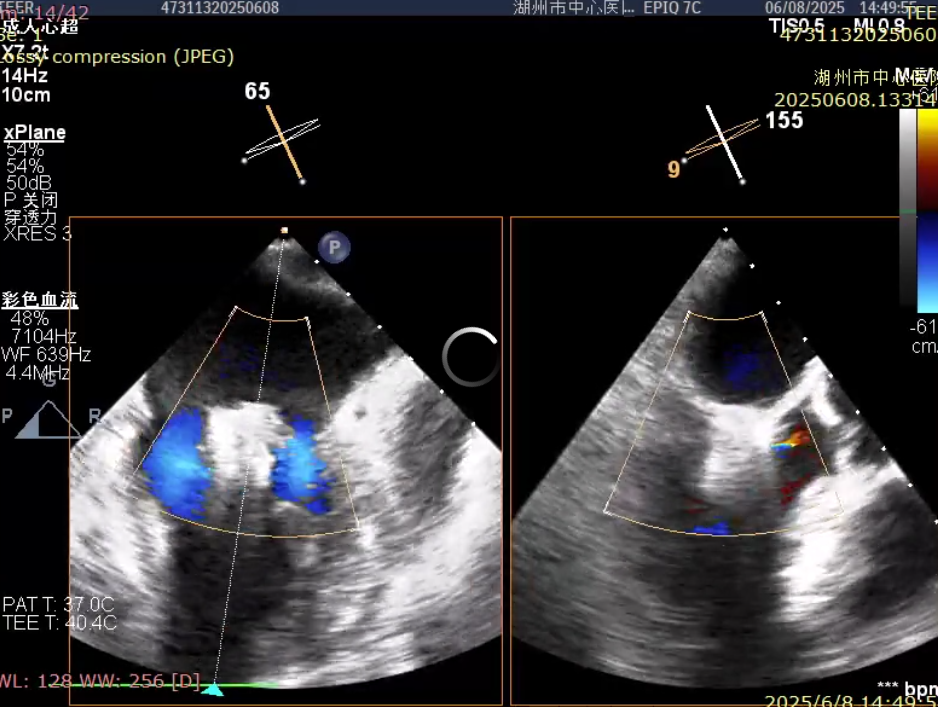

79 岁的李奶奶因活动后胸闷、血压偏低入院,心超提示二尖瓣脱垂伴重度返流,左房压力高达 45 mmHg,常规药物治疗无效。考虑到患者高龄、瘦弱且基础病多,团队选择经导管二尖瓣钳夹术。术中,在超声实时引导下,通过股静脉送入钳夹装置,精准夹合脱垂瓣叶,左房压力即刻降至 12 mmHg。